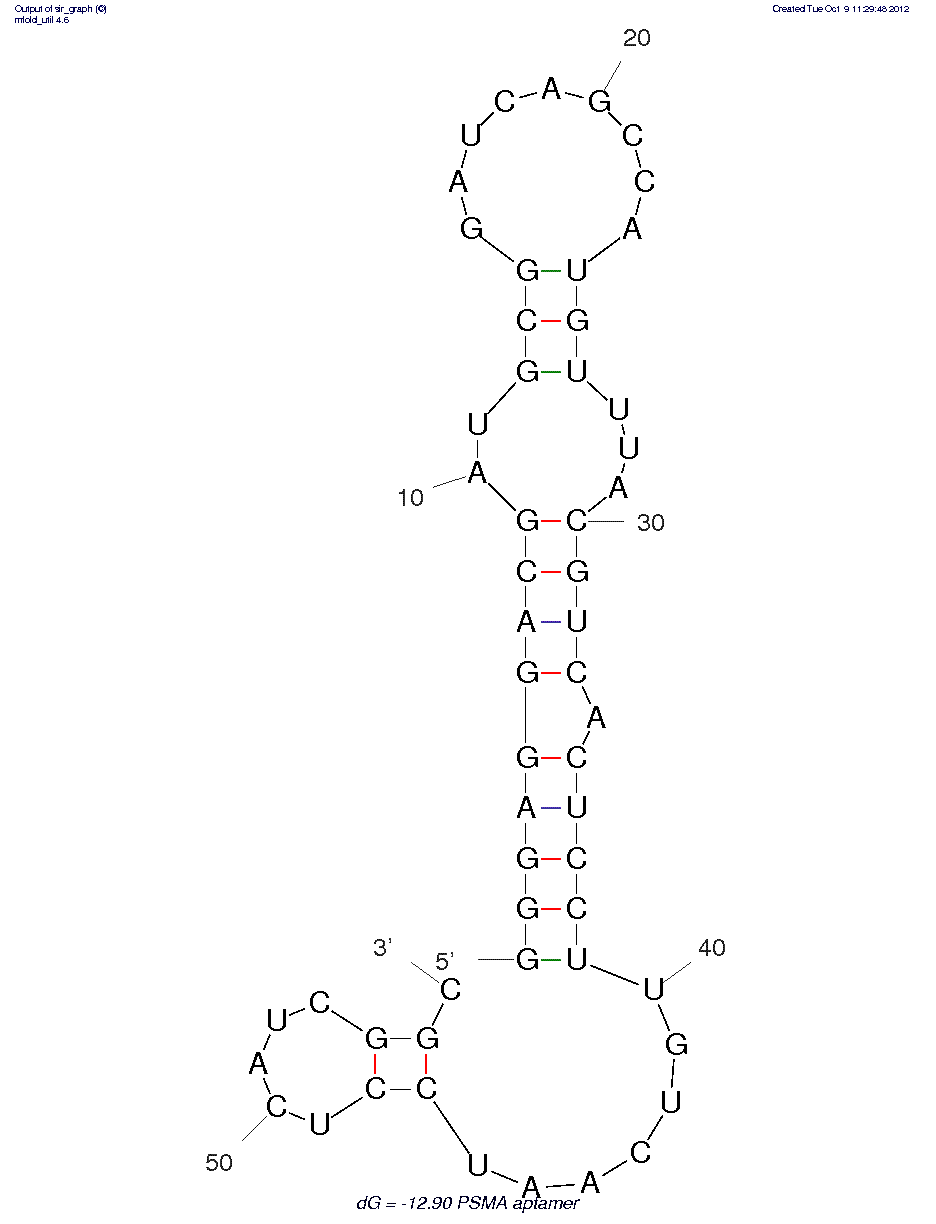

DNA

Protein

40

N/A nM